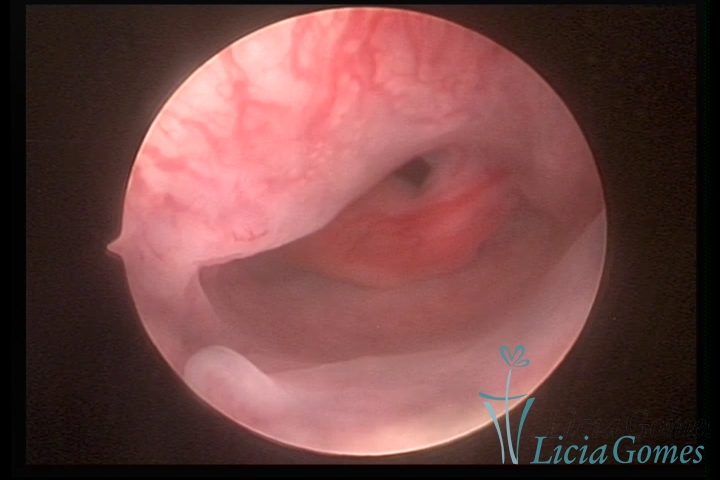

PÓLIPOS ENDOCERVICAIS

São tumores benignos, resultantes da proliferação focal reativa aos processos inflamatórios ou à situações de hiperestrogenismo, e podem ter sésseis (com a base de implantação larga) ou pediculados do epitélio.